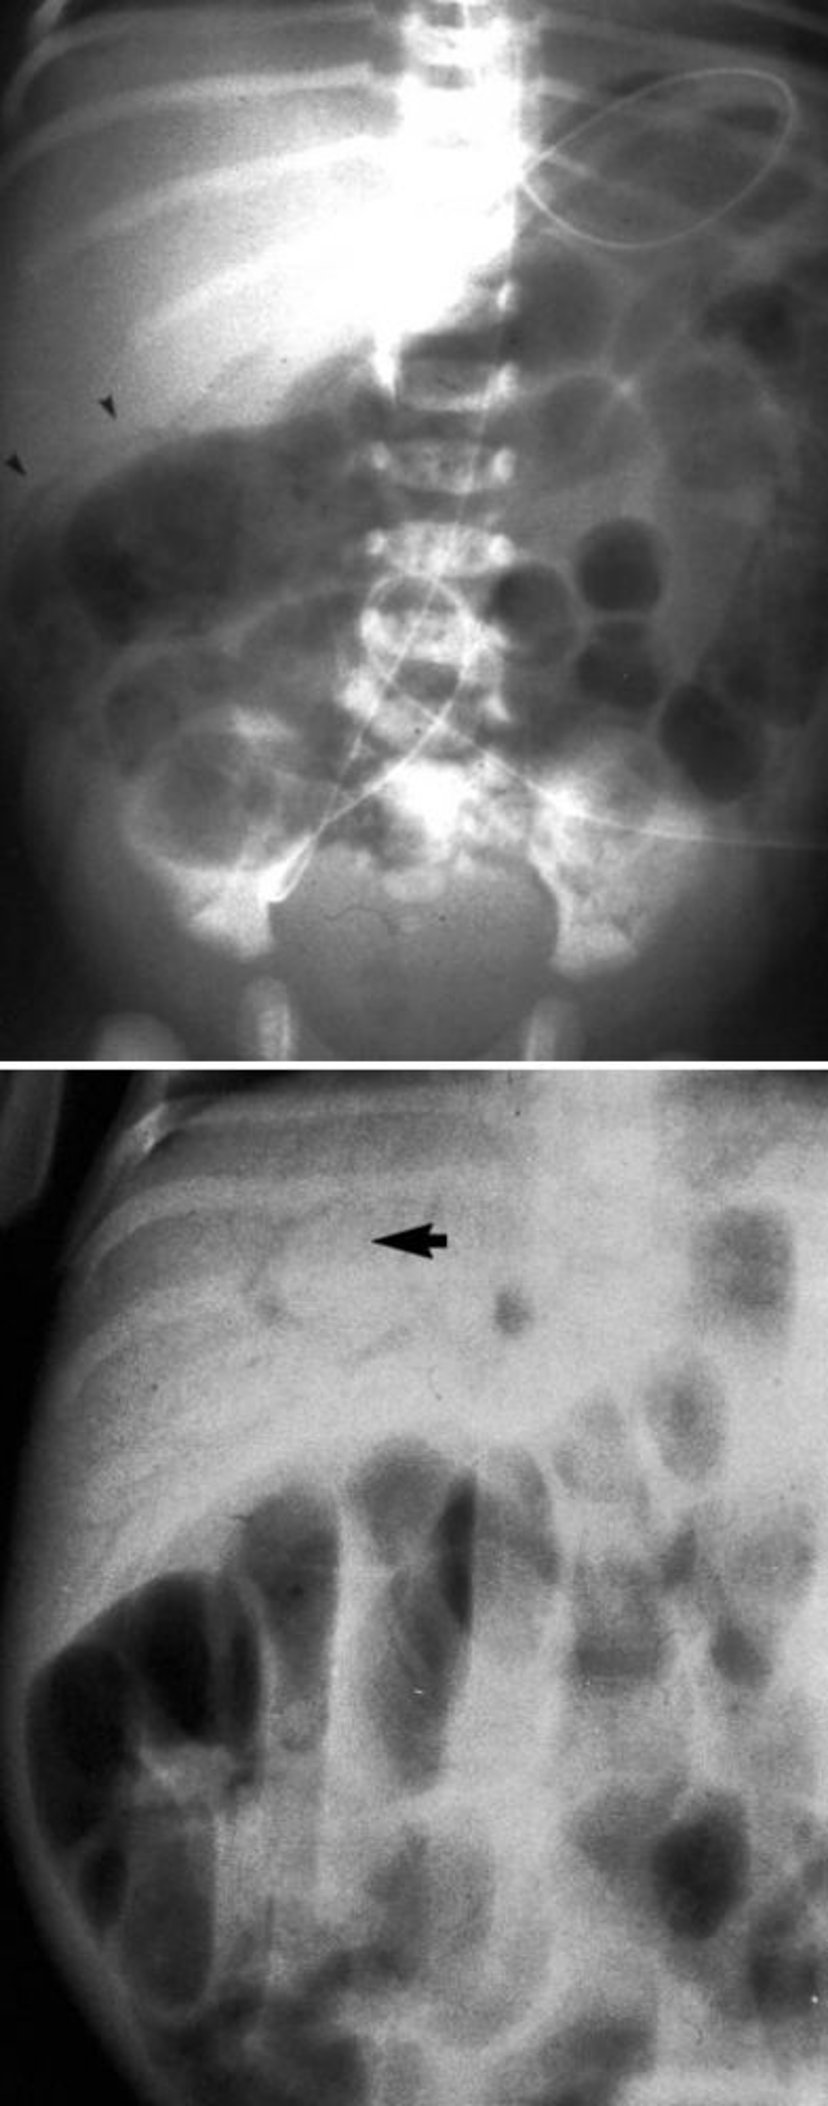

Đặc điểm X-quang của viêm ruột hoại tử

Hình ảnh này cho thấy khí trong ruột (đầu mũi tên) và trong tĩnh mạch cửa (dưới, mũi tên).